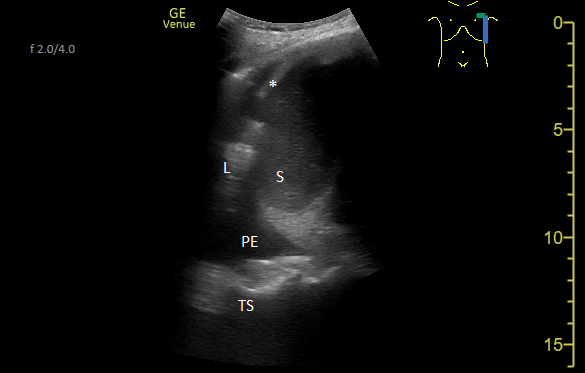

Un patient de 90 ans connu pour une insuffisance cardiaque chronique d’origine rythmique et ischémique se présente aux urgences en raison d’une fatigue et une dyspnée d’effort s’aggravant depuis plusieurs jours, malgré la majoration de son traitement diurétique.  L’examen clinique est dans la norme, hormis une légère hypertension à 153/85mmHg et la présence d’œdèmes des membres inférieurs. L’électrocardiogramme retrouve une fibrillation auriculaire à 63/min et un hémibloc antérieur gauche connus. Au bilan sanguin, il n’y a pas de syndrome inflammatoire ni d’ischémie myocardique, l’hémoglobine est abaissée à 100 g/L (anémie microcytaire connue et stable) et le NT-proBNP s’élève à 3'000 ng/L (N < 300). La radiographie pulmonaire effectuée en position semi-assise n’est pas conclusive (absence de franc signe de surcharge ou épanchement visualisé, micro-infiltrats éparses sus-diaphragmatique bilatéral sans signe de la silhouette).

Une échographie pleuro-pulmonaire ciblée est effectuée. On visualise cette image en région thoracique latéro-postéro-basale gauche :